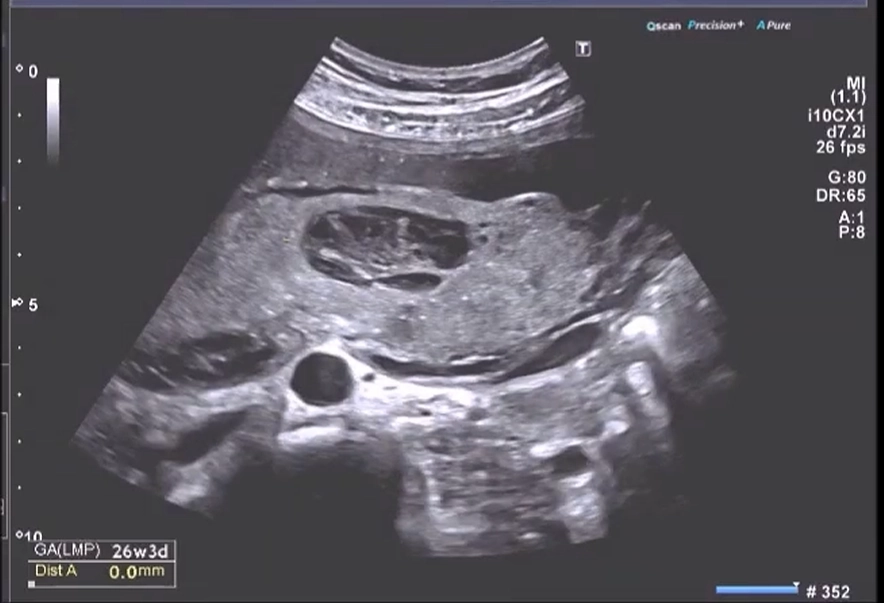

Nhau cuộn mép (Circumvallate Placenta)

16/03/2026